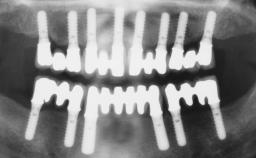

Replacement of Two Teeth in a Partially Dentate Posterior Maxilla with a Fixed Dental Prosthesis Using a Conventional Loading Protocol

In September of 1995, a 64-year-old female patient presented to our clinic with a distally shortened arch in the left maxilla and the desire for a fixed rehabilitation. The patient’s medical history did not reveal any major issues, and she did not take any significant medication. She was a non-smoker and did not report any allergies.The patient wished to restore her chewing function on the left side, which was severely compromised due to the missing teeth 25, 26, and 27. The antagonistic lower teeth were present and in acceptable condition.